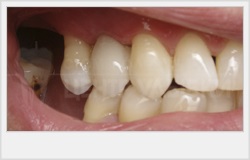

uite pacient la recuperarea tehnicii dinte lipsă

Povestea mea este un medic dentist a început acum 6 ani, într-o luptă inegală, am pierdut dintele de sus. răni lins, a decis să restaureze dintele pierdut. O vizita clinici sumă decentă, am identificat un număr de opțiuni pentru mine:

Primul și al doilea nu vin din mai multe motive. Dar lucrul cel mai important. În primul caz, nu am vrut să-l omoare dinții adiacenți, și implanteze bugetul meu modest nu a putut rezista. Prin urmare, decizia pe care am decis rapid în favoarea unui pod adeziv.

adeziv meu ma mostsluzhit timp de 4 ani. dar am decis să-i spun chiar acum, vizitând medicul dentist pentru un control de rutina.